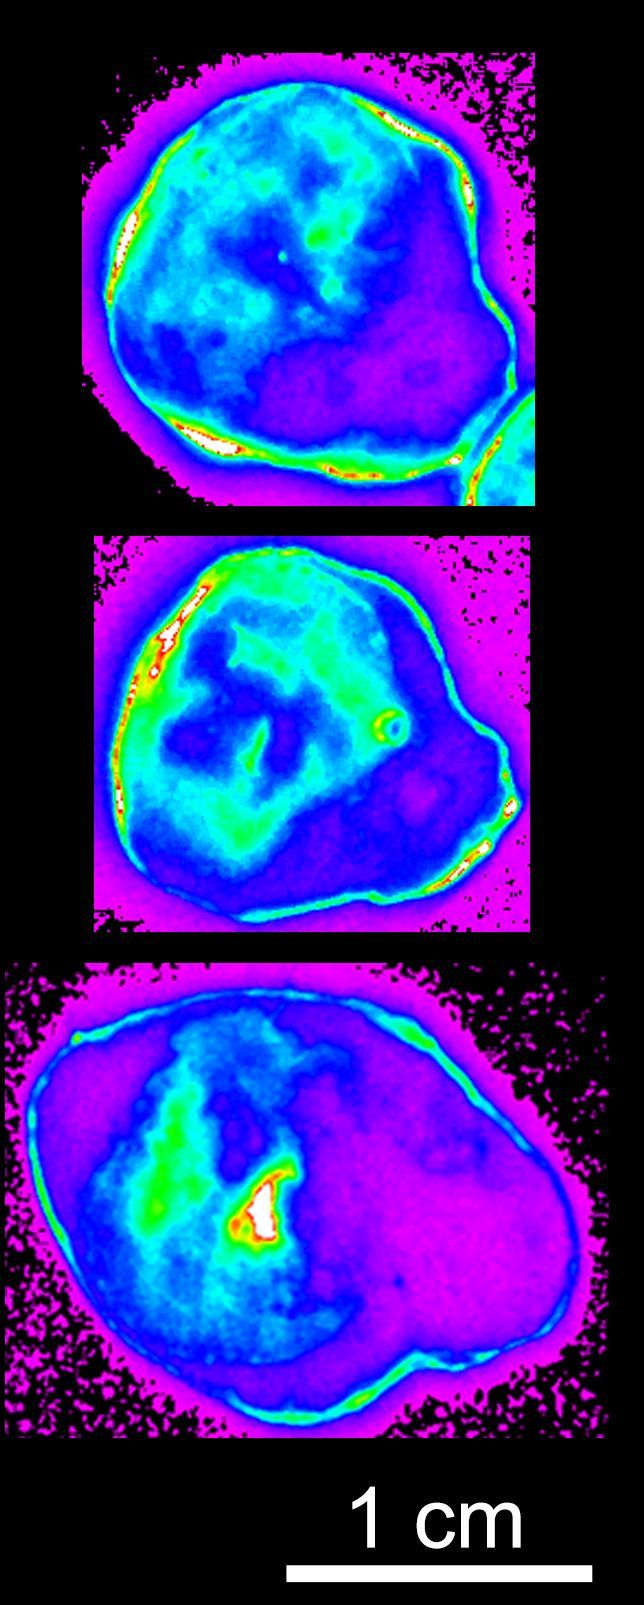

"Imagine you're a surgeon tasked with removing a tumor located near a vital organ. Your goal is to remove all the cancerous tissue while preserving everything essential to the patient's quality of life," explains Tomáš Etrych. Together with his team, he developed a polymer probe carrying a fluorescent label that literally illuminates tumor margins, significantly aiding surgeons and improving the course of treatment.

Additionally, the probe can be equipped with molecules that selectively bind to tumor tissue receptors, actively guiding it to the target site. Specific mechanisms can also activate the fluorescent signal only once the target is reached, further improving tumor margin precision. This targeted fluorescent polymer has potential use not only for visualizing tumors but also for identifying inflammatory tissue.

The polymer is currently being tested in collaboration with the Department of Otorhinolaryngology and Head and Neck Surgery at the First Faculty of Medicine, Charles University and Motol University Hospital, as well as other clinical institutions. The patent covers the structure of the polymer probe, its properties, and its intended applications. At present, the search for a commercial partner capable of bringing the technology to clinical practice is underway.